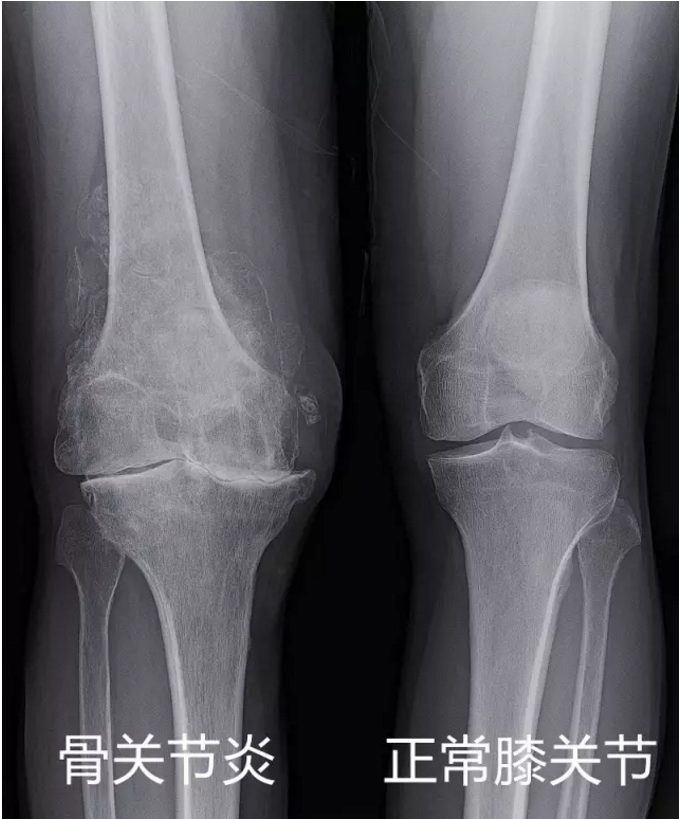

2. 常伴有骨关节炎:很多老年人的膝盖本身已经有不同程度的软骨磨损(骨关节炎)。半月板撕裂可能是关节炎进展的一部分,而不仅仅是孤立的问题。

· 关节炎的严重程度:这是决定性因素之一。如果X光片显示关节间隙已经严重狭窄,软骨磨损殆尽,那么单纯的半月板手术效果可能很差,因为疼痛主要来源于关节炎。此时可能需要考虑膝关节置换术,而不是单纯的半月板手术。

· X光显示严重的骨关节炎(关节间隙几乎消失)。此时半月板手术意义不大,应直接考虑关节置换评估。